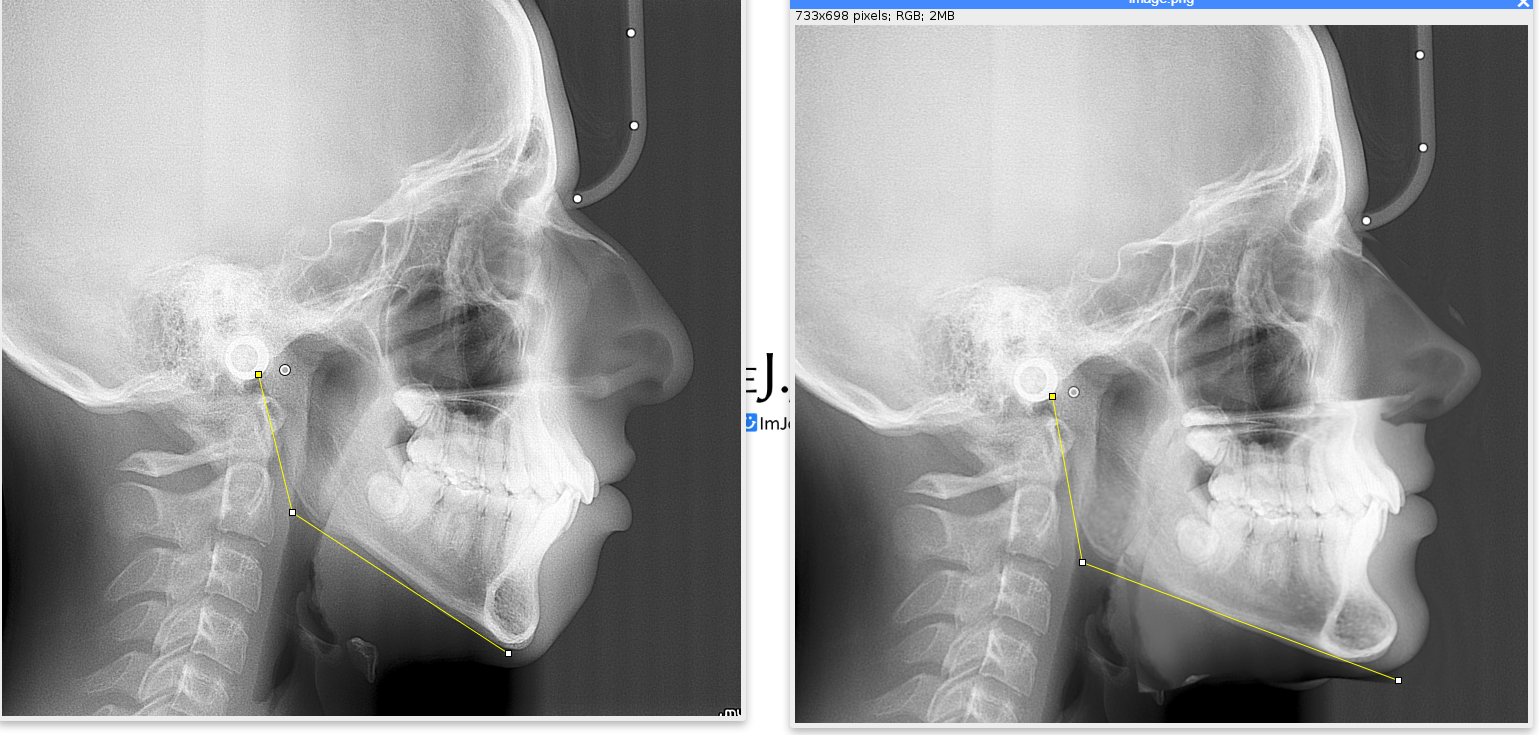

i had gotten 12* ccw trimax with great projection and a rhinoplasty

what if i didnt get camouflaged and underwent djs by now

had rhino but theres no fucking way im only getting genio and implants for my jaw